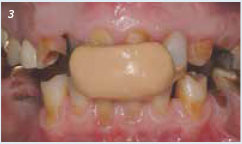

Bij de intake bij de tandarts is sprake van een ernstige gebitsmutilatie met diastemen, radices relictae en functionele problemen ten aanzien van kauwfunctie, fonetiek en esthetiek (afbeelding 1). De 12 is endodontisch behandeld en vertoont geen apicale pathologie.

Bij de intake: slijtage van boven- en onderfront, radices in 3e en 4e kwadrant, beethoogteverlies en geen dorsale afsteuning.